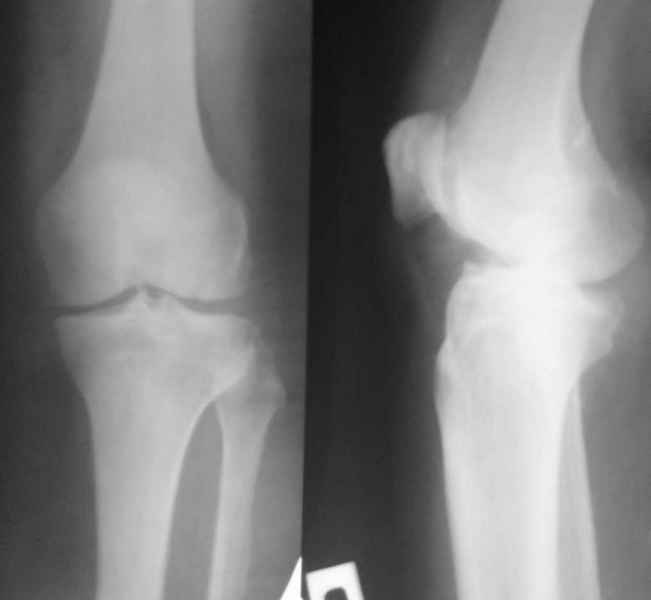

Судя по первому снимку возникает вопрос - а надо было?

Уважаемый Андрей, действительно по снимку до операции сустав кажется сохранным. Но этой пациентке за несколько месяцев до операции была выполнена артроскопия, задокументировано отсутствие хряща на суставных поверхностях внутренних мыщелков бедренной и б\б костей. Этот снимок сделан без нагрузки и поэтому создается впечатление "сохранного сустава". Если бы был сделан снимок до операции с нагрузкой, вашего вопроса не было бы.

Надо было протезировать такой сустав? Может быть у меня на компьютере не очень хорошее разрешение, но мне показалось, что сустав еще сохранный и можно было полечить более консервативными методами - артроскопия, хондропротекторы. Хотя я знаю, Александр Николаевич, Ваше отношение к ним.